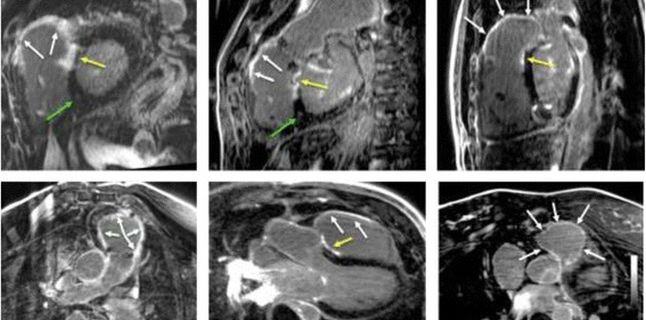

Rezonanta magnetica (RM) cardiovasculara (Cardio-RM) este cea mai avansata metoda imagistica de evaluare a functiei inimii. La Emerald, investigatia este realizata de o echipa formata dintr-un medic radiolog cu experienta si un medic cardiolog specializat in RM cardiovasculara, in timpul acesteia fiind preluate peste 1500 de imagini de pe inima.

Este indicata in cazul urmatoarelor patologii: boli congenitale de cord, boala cardiaca ischemica, infarct miocardic acut sau cronic (evaluarea cicatricilor / viabilitatii miocardice), evaluarea parametrilor de severitate si studiul cauzelor de insuficienta cardiaca, cardiomiopatie hipertrofica sau dilatativa (inclusiv analiza extensiei, aspectului, intensitatii si localizarii fibrozei miocardice in anumite tipuri de cardiomiopatii), miocardita, cardiomiopatie aritmogena de ventricul drept, studiul substratului morfologic al unor tulburari de ritm cardiac, detalii asupra miocardului in diferite tipuri de cardiomiopatii infiltrative (talasemie, hemocromatoza, amiloidoza, sarcoidoza, Boala Fabry), patologie vasculara cardiaca, evaluarea tumorilor cardiace.

• Evalueaza nu doar functia miocardica, pentru care este o metoda de inalta eficienta, ci si structura (morfologia) peretelui inimii, intr-un mod mai eficient fata de ecografie sau de computer-tomografia cardiaca (CT). Astfel poate delimita exact cat de extins este un infarct, ca suprafata cat si profunzime in grosimea muschiului cardiac. De asemenea detecteaza tesutul cicatricial (fibroza) care apare in diverse cardiomiopatii si ajuta la diferentierea intre acestea. Poate detecta si continutul de apa (edem) al miocardului, si face diferenta intre evenimente cardiace recente si vechi. Ajuta si in diagnosticul tumorilor intracardiace. Este esentiala in analiza anatomiei si hemodinamicii la pacientii cu boli congenitale.